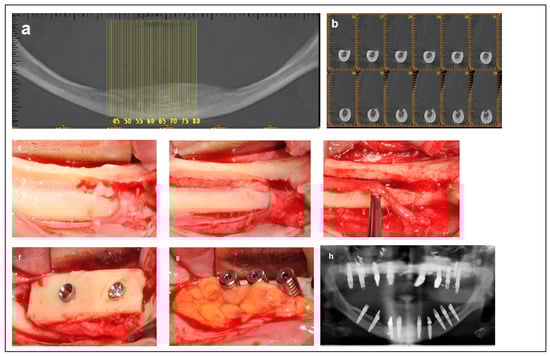

2.3. Category 3

2.4. Category 4